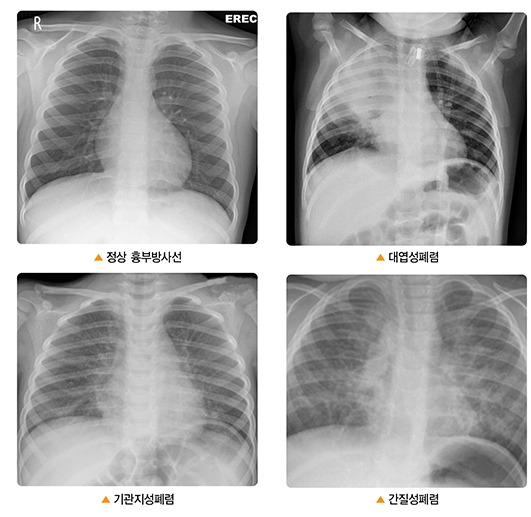

폐렴이란 무엇인가?

폐렴은 폐에 염증이 생기는 질병으로, 다양한 원인에 의해 발생할 수 있습니다. 주로 세균, 바이러스, 곰팡이 등이 원인이 되며, 특히 독감 바이러스에 의해 유발되는 경우가 많습니다. 폐렴은 기침, 발열, 호흡 곤란 등의 증상을 동반하며, 심각한 경우에는 생명을 위협할 수 있습니다.